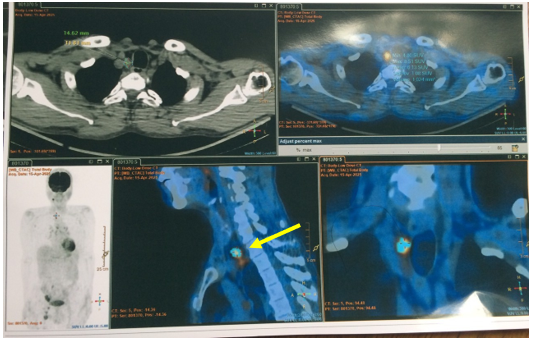

- PET/CT (Tháng 03/2025): Không thấy tổn thương tăng hấp thu FDG khu trú bất thường tại hạ họng. Hình ảnh hạch nhóm 1R, kích thước 12x15mm,tăng chuyển hóa glucose, khả năng do di căn. Đề nghị đối chiếu với mô bệnh học. Hình ảnh tổn thương giảm tỉ trọng kèm vôi hóa kích thước ~33x50x39mm, tăng chuyển hóa glucose ở hạ phân thuỳ VII gan, tương ứng với tổn thương gan đã nút mạch, theo dõi tiến triển. Hình ảnh nhiều hạch ở dọc theo động mạch chậu chung và chậu ngoài phải, bẹn phải, tăng chuyển hóa glucose. Đề nghị đối chiếu với mô bệnh học. Chưa phát hiện hình ảnh tăng hấp thu FDG bất thường, khu trú tại các vị trí khác trên xạ hình PET/CT toàn thân.

Hình 5: Hình ảnh hạch nhóm 1R, kích thước 12x15mm, tăng chuyển hóa glucose (SUV max 8,5), khả năng do di căn.(mũi tên vàng)

Hình 6: Hình ảnh hạch bẹn, kích thước 14x29mm, SUV max 8,9 (mũi tên vàng)